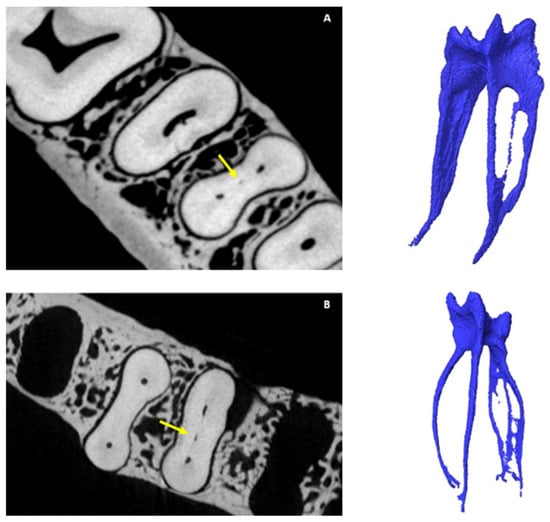

3.4. Chamber Canals

3.5. Accessory Canals (ACs)